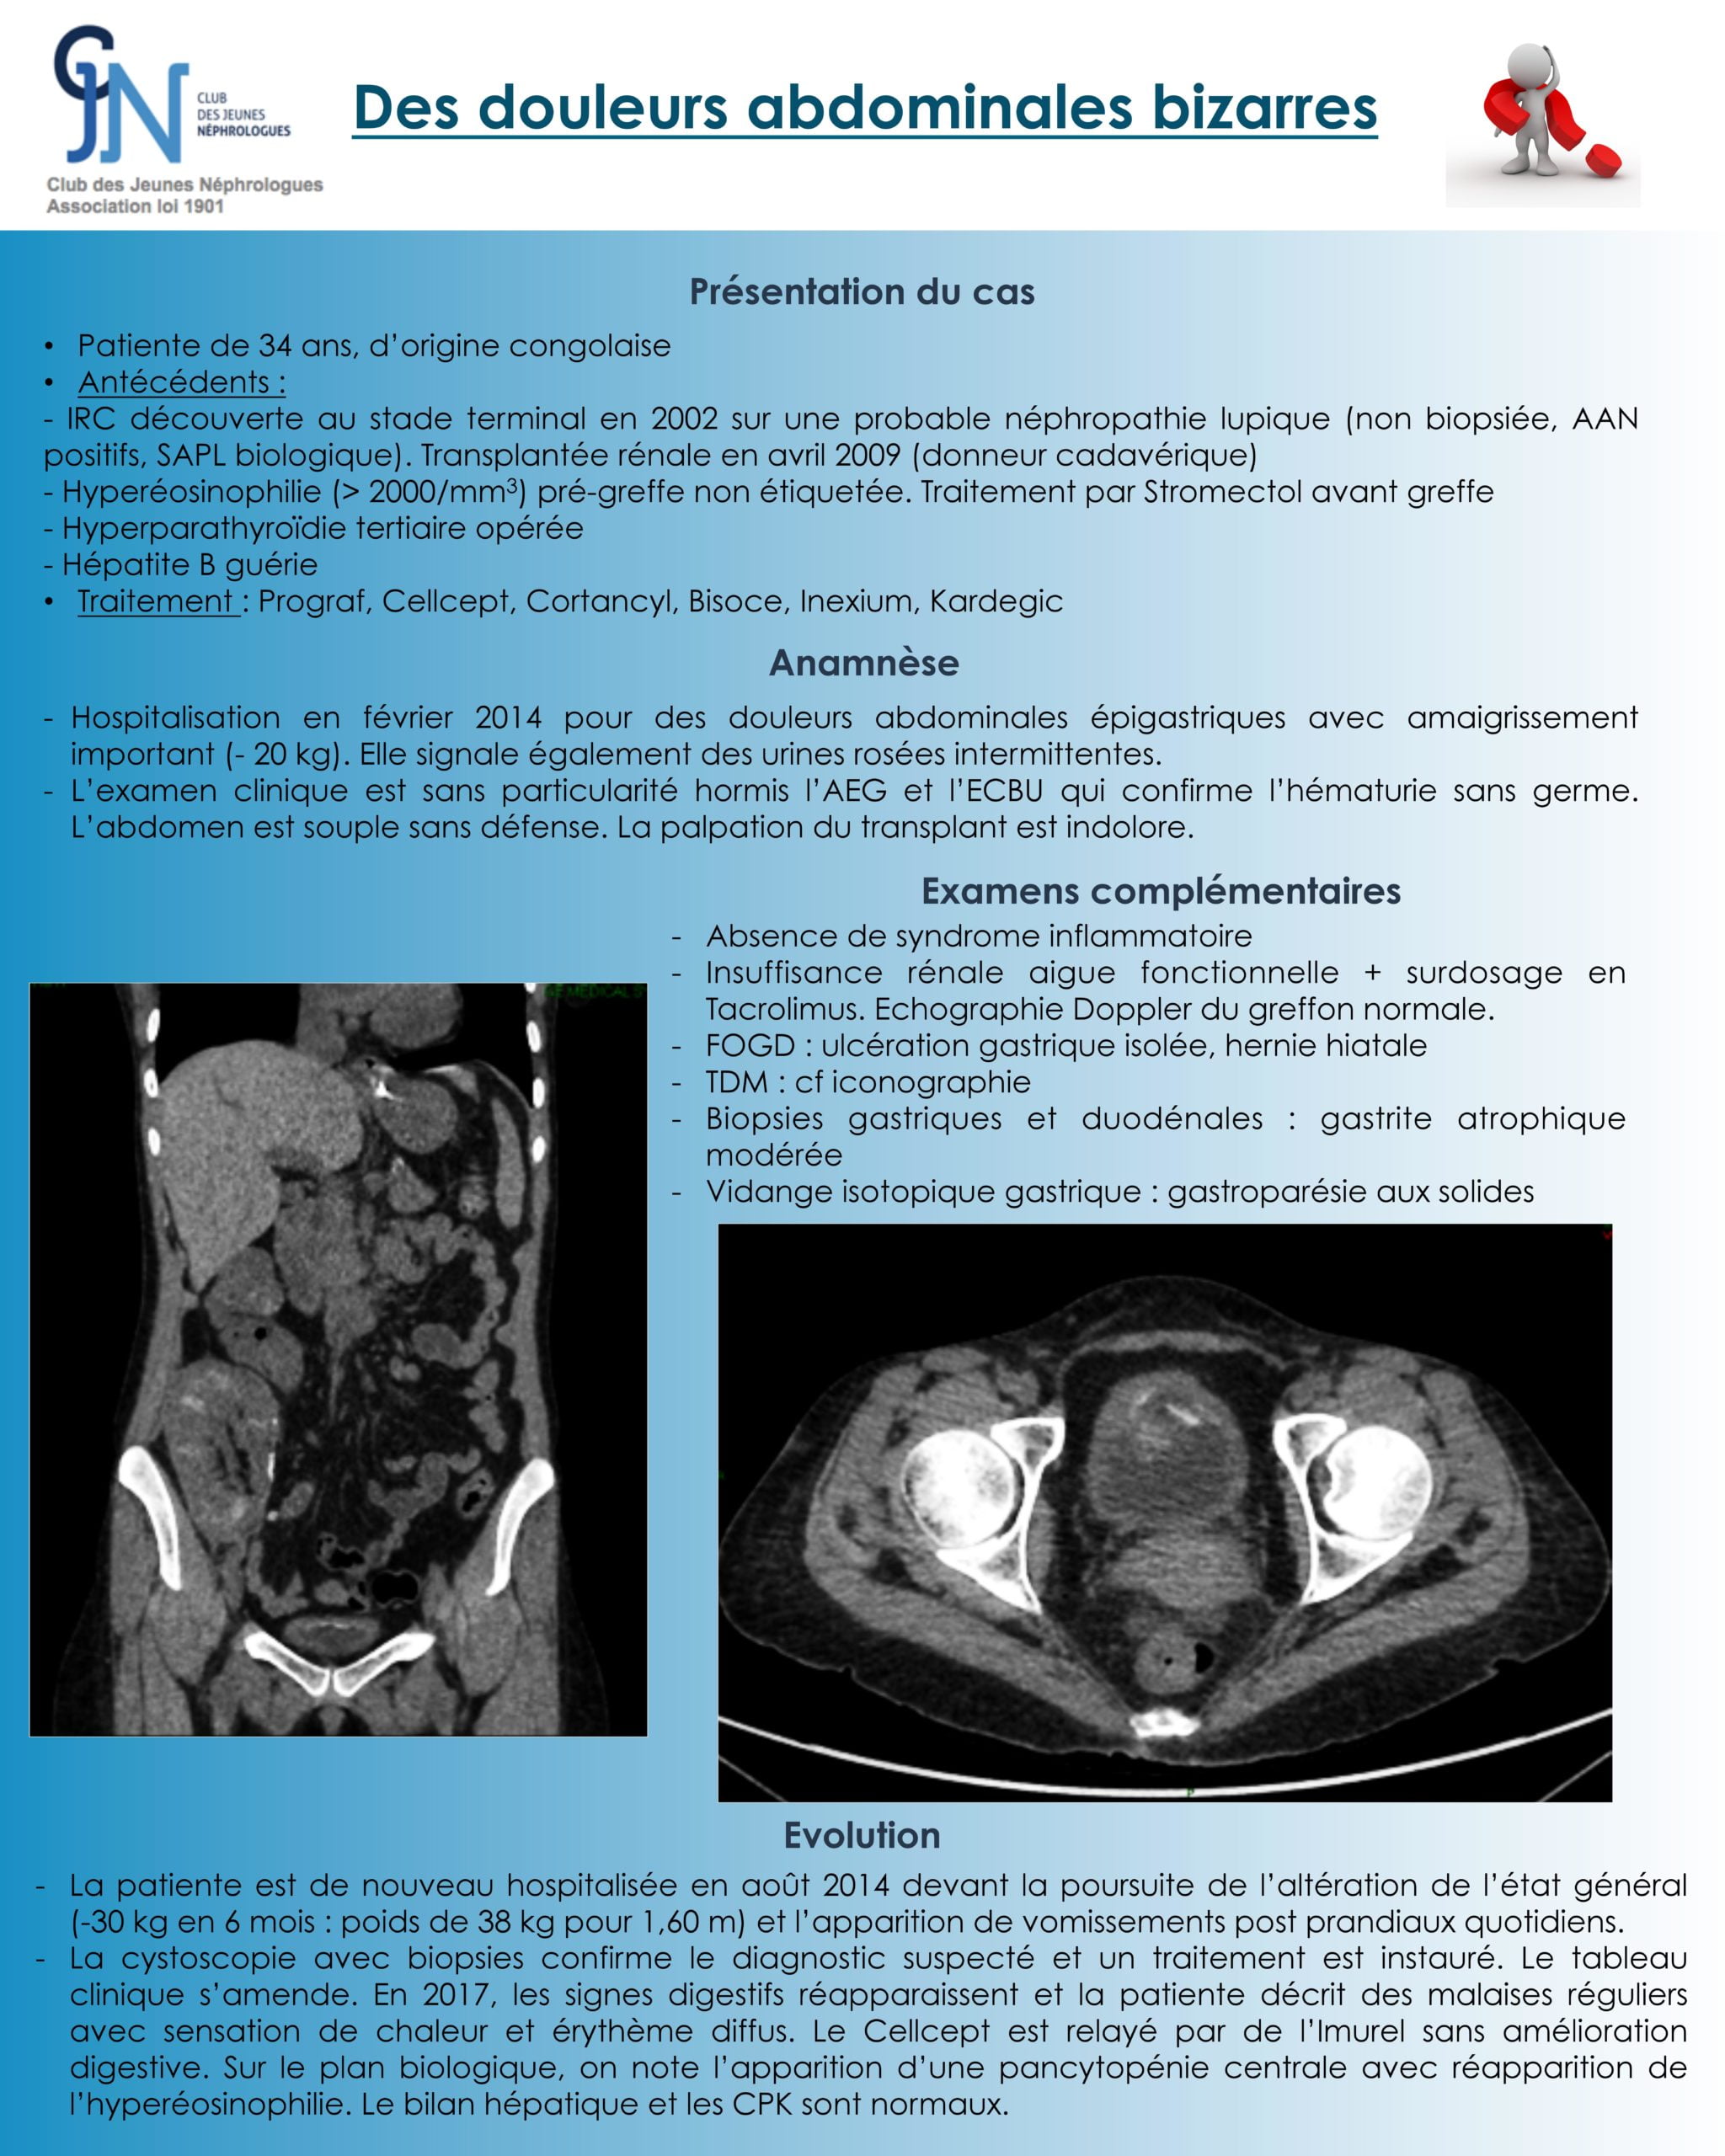

La deuxième patiente, transplantée rénale avait une symptomatologie digestive avec hématurie macroscopie intermittente et vessie porcelaine (cf. tomodensitométrie).